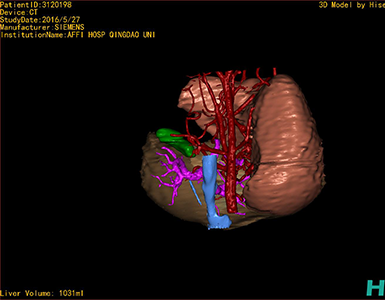

CT结果输入海信CAS系统后行3D重建及手术规划后,于2016-6-28全麻下行“劈离式肝移植(左半肝,背驮式)”手术治疗。

将0.625mm双源薄层CT资料的静脉期和动脉期Dicom格式文件导入海信CAS系统。

通过调节窗宽窗位调整CT序号,对肝实质,胆囊,下腔静脉,肝动脉、门静脉及肝静脉等进行三维重建,明确血管走行;系统自动计算肝脏体积。

模拟手术操作,肝脏体积为1052ml,通过比对11-12岁正常肝脏体积为1116.86±158.78ml,建议进行肝移植手术。

术前手术方案的规划。

术前三维重建:

重建图片